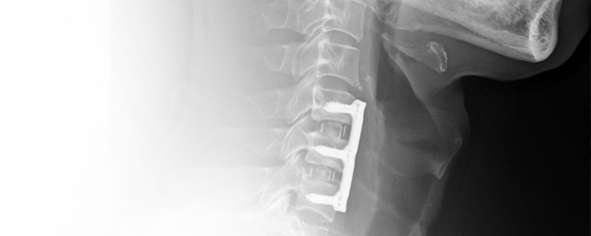

當頸椎被固定融合後該節椎間盤上下兩節椎骨融合為一,頸椎少了一個活動的關節,必需由鄰近節椎間盤增加活動度來代償,若有多節的手術情況更為嚴重,幾年後常有「鄰近節病變」的發生,即上下節的椎間盤因工作量增加較容易退化、突出,讓患者再度產生神經壓迫,症狀復發,甚至需要再次椎間盤切除手術治療。人工椎間盤(圖六、七、八)即是近年來科技進步的產物,在切除病變的椎間盤後,用人工椎間盤植入此空隙,藉以保留此病變節脊椎的活動度,可降低鄰近節病變的產生。

人工椎間盤在2006年台灣衛生署核准開始使用,經過十多年的使用經驗效果很好,確實可降低鄰近節病變的產生,多年來價格一直沒下降,目前我們使用的最新一代的Prodisc C vivo (圖九),此產品裝置容易,可以明顯降低手術的風險及縮短手術時間,又不用戴頸圈,但一個是25萬5千元。雖然在2021年12月起C4-5及C5-6可以向健保局申請,但由於經費有限、條件很嚴格,能申請通過給付的很少,申請條件請查臉書 "陳建良神經外科"。

圖六

圖七

圖八

圖九